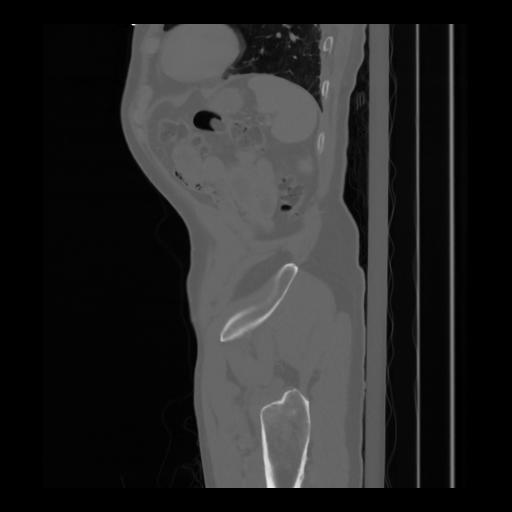

36 CUERPO,CE,Sagittal,3.000,CUERPO,Sagittal,